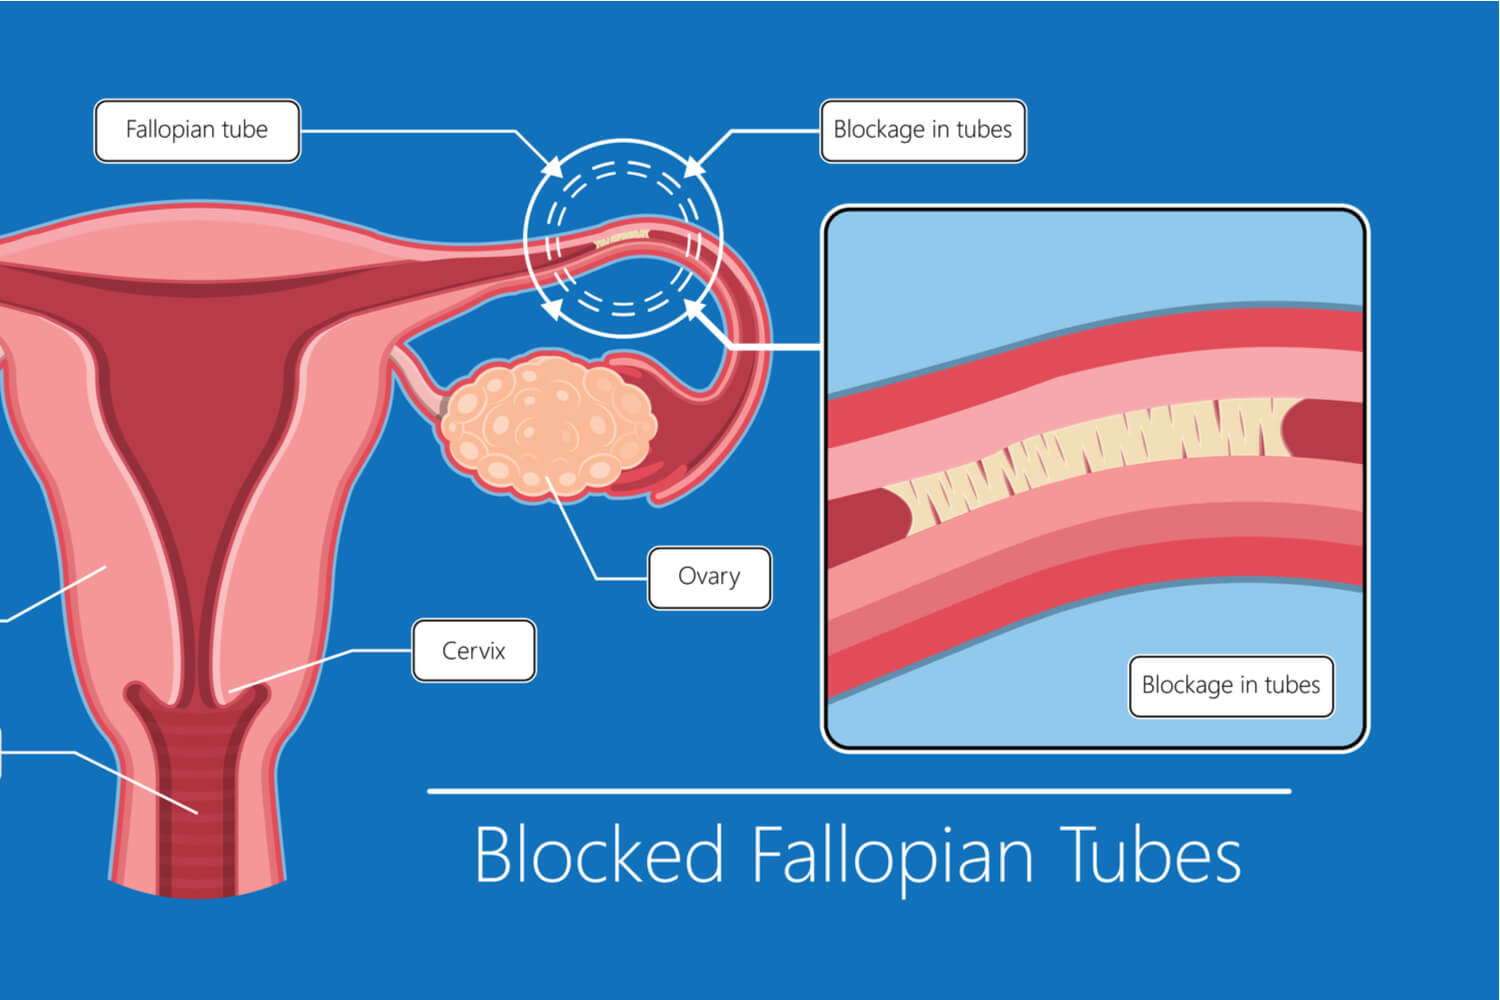

Tubal Blockage Causes Symptoms Treatments Our Approach

Blocked Fallopian Tubes Causes Symptoms And Treatment

Blocked Fallopian Tubes Symptoms Causes And Treatment

FTR Symptoms And Causes Of Blocked Fallopian Tubes Fibroid